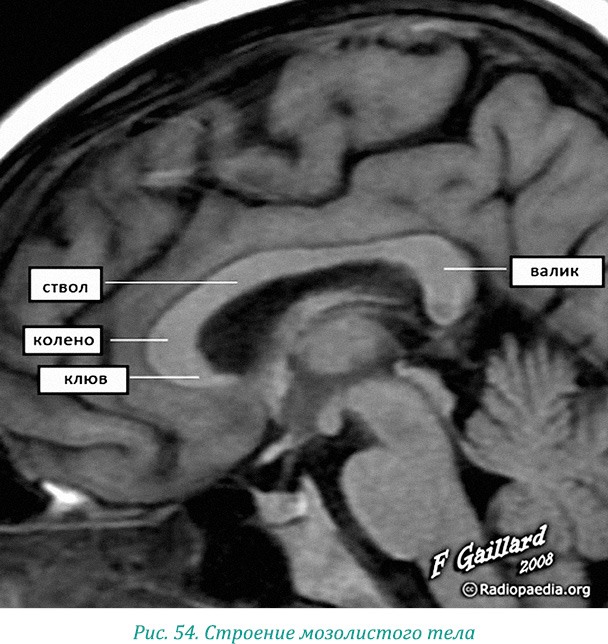

Наша голова представляет собой то самое яйцо, снесенное Эвриномой, его маленький фрактальный осколок (рис. 52). Поэтому дракончик мозолистого тела – это самый мощный «мост» между правым и левым полушариями, состоящий из более чем 200 миллионов нервов (рис. 53).

У здоровой группы испытуемых скорость реакции в тесте на чтение слов была статистически связана с активностью заднего отдела мозолистого тела (его называют валиком – рис. 54). Как отмечают неврологи, это кратчайший путь между зрительным центром в одном полушарии и речевым в другом.

Валик – это «голова дракона», нависающая над эпифизом. Нырнув «валиком» в наше тело, мозолистое тело отпечаталось на позвоночнике. Поэтому наш крестец и копчик похожи на голову змеи (рис. 55), а спинной мозг и позвоночник являются ее телом.